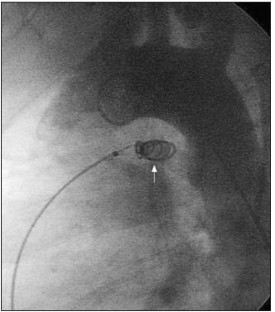

Figure 1.